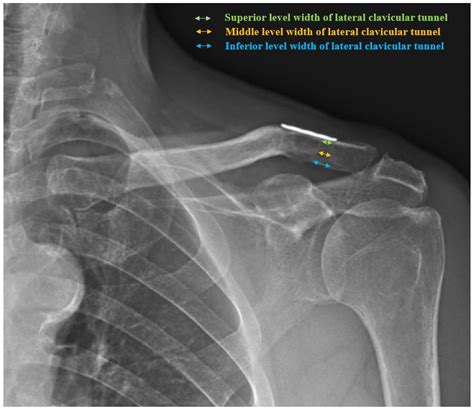

Interpreting the results of an Ac Joint X Ray requires a trained eye. Radiologists look for specific signs and abnormalities that indicate various conditions. Here are some key points they consider:

• Joint Space: The space between the clavicle and scapula should be uniform. Any narrowing or widening can indicate injury or degeneration.

• Bone Alignment: The bones should be properly aligned. Any displacement or misalignment can suggest a fracture or dislocation.

• Bone Density: Changes in bone density can indicate conditions like osteoporosis or bone tumors.

• Soft Tissue: While X-rays primarily show bones, they can also reveal some soft tissue abnormalities, such as swelling or calcification.